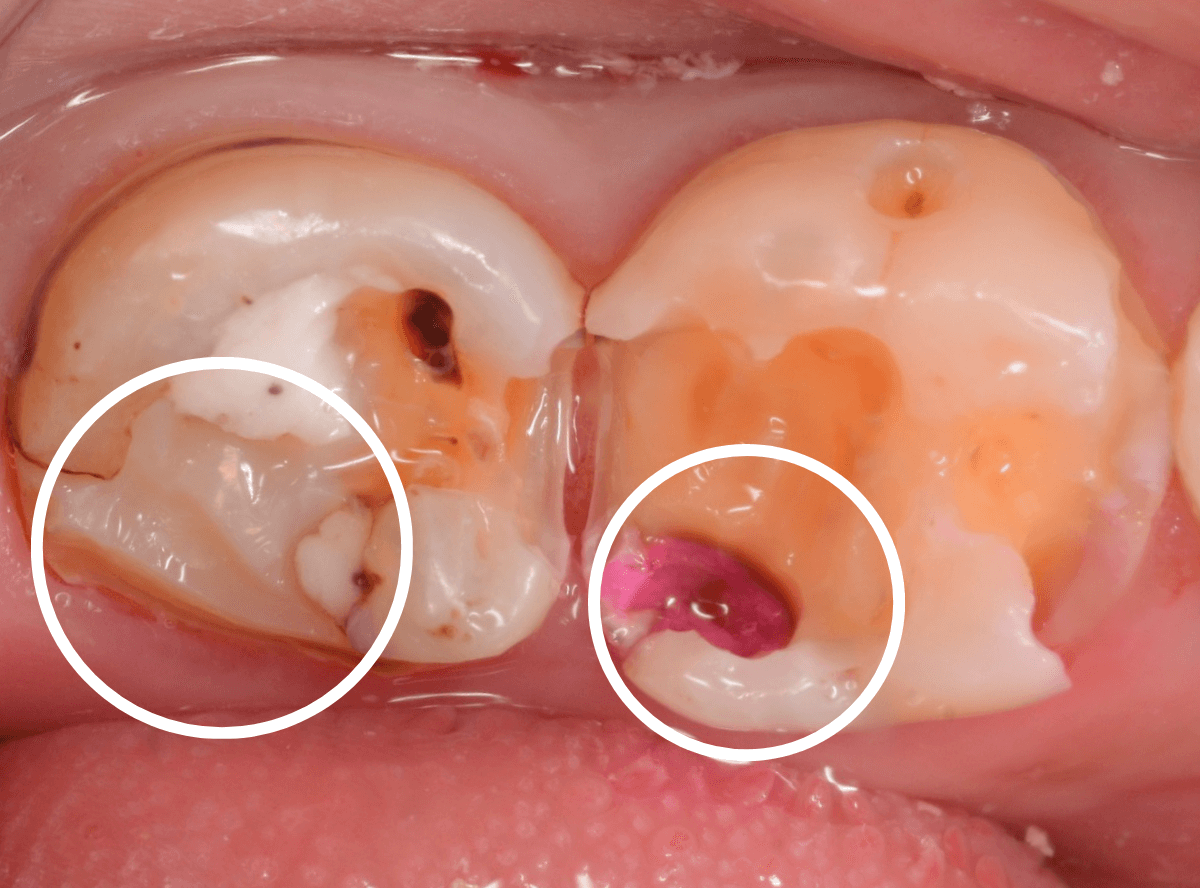

慎重に全ての虫歯を除去したところです。

〇部が神経の入り口が見えているところです。

神経を保護する処置をして、しばらく経過観察しますが、痛みが出て神経を除去する必要が出る可能性も高いです。

痛みが出ませんように・・・。